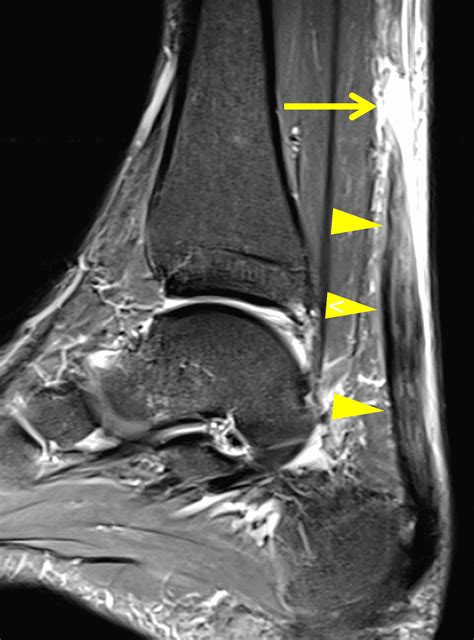

Achilles Tendon Tear | Radsource

Achilles Tendon Tear | Radsource